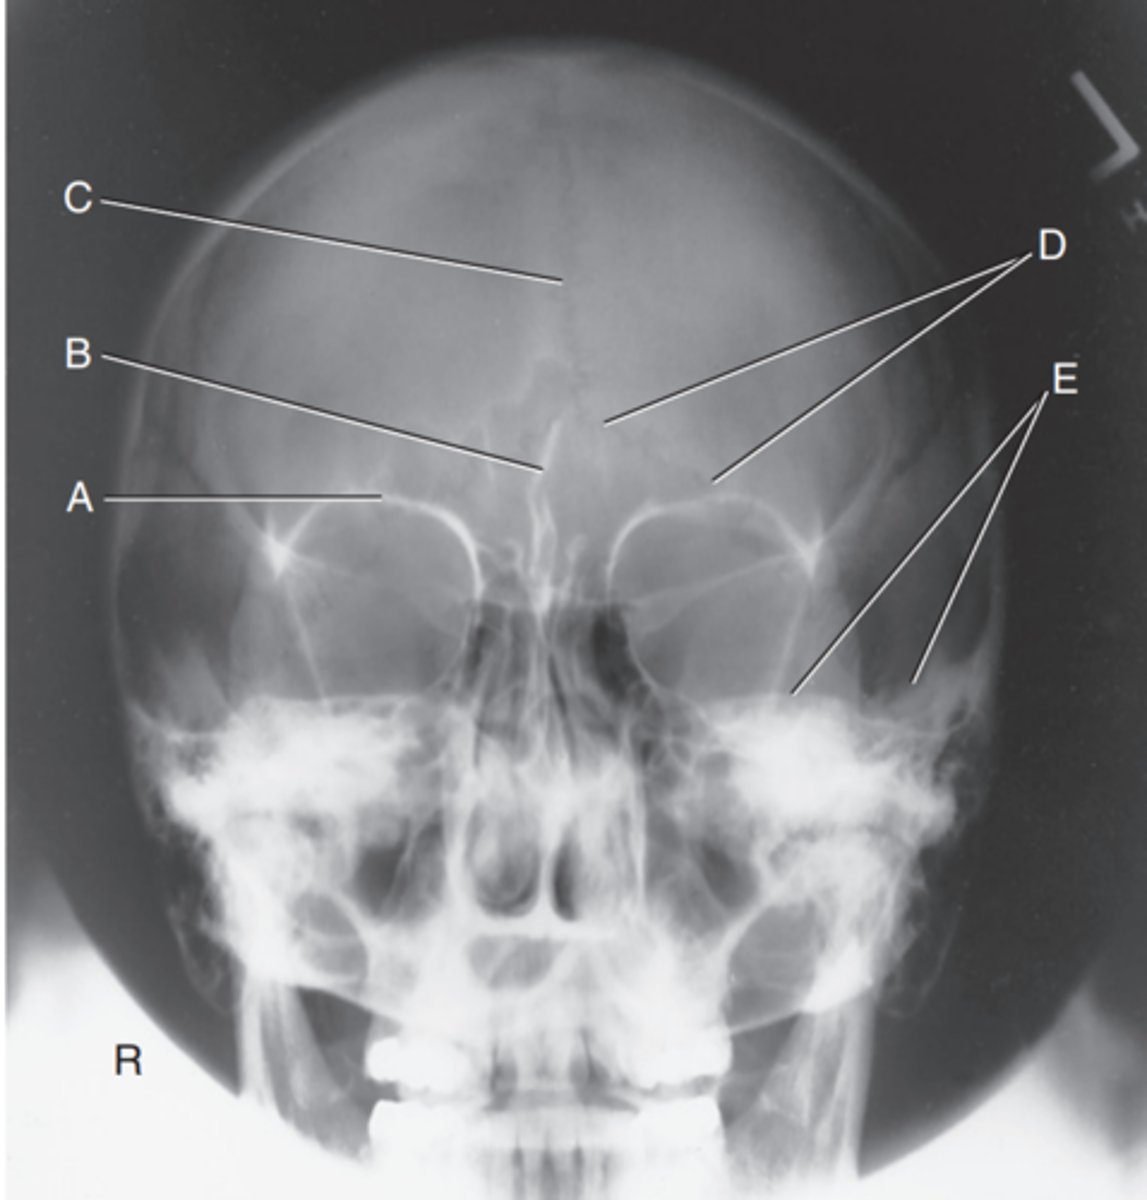

Supraorbital margin of right orbit

Label A

Crista galli of ethmoid

Label B

Sagittal suture

Label C

Lambdoidal suture

Label D

Petrous ridge

Label E